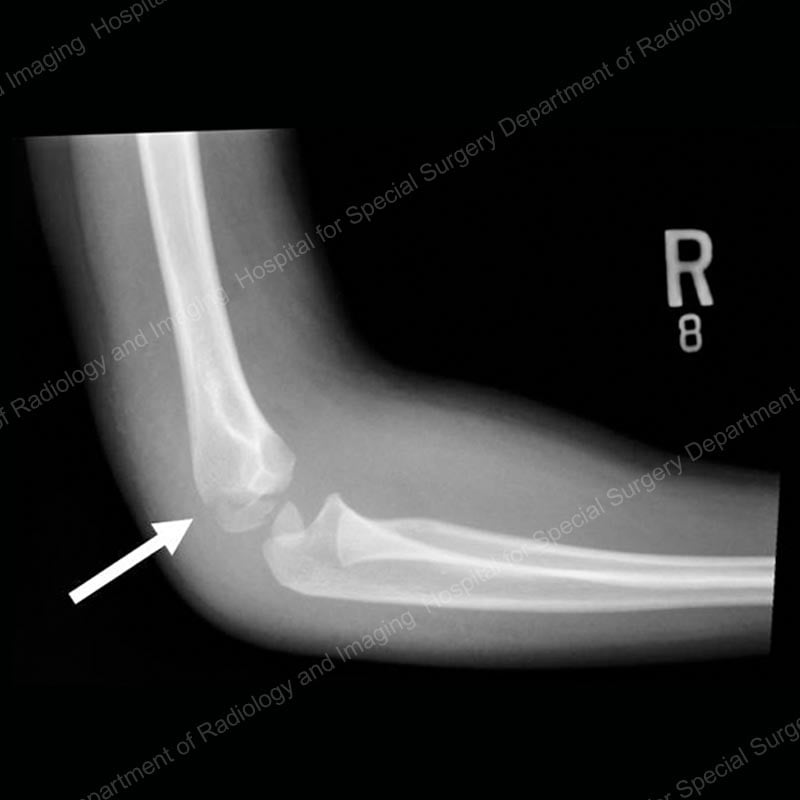

Lateral condyle fractures

These breaks occur at the outer part of the elbow, an area that serves as an attachment point for most of the muscles that straighten out the wrist and fingers, and also for the ligaments that stabilize the elbow joint. Lateral condyle fractures usually result from relatively low energy injuries, and the growth plate of the elbow typically resumes normal growth after the .

Figure 4: Lateral (side) X-ray view of a lateral condyle fracture prior to treatment. The arrow points to the fracture line.

Orthopedic surgeons classify these injuries based on the degree to which they are displaced and determine treatment accordingly. If the fracture is non-displaced, that is, the fracture line can be seen on an image, but the bone has not shifted out of position, the patient may only require immobilization of the arm in a splint or cast. However, if any displacement is found, the bone needs to be realigned and stabilized with pins or wires as in supracondylar fractures. (Please see Figure 2 for an example of this type of wiring.) This surgery may or may not require an incision, depending on the extent of the displacement.